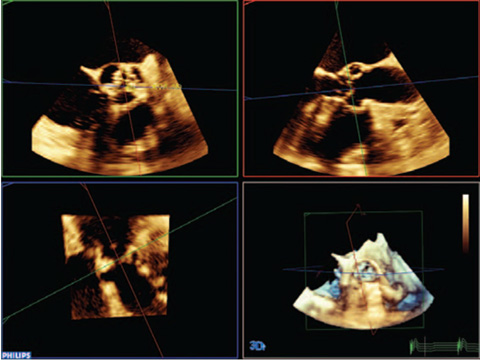

Функция интеллектуального определения анатомических структур изучает данные УЗИ пациента и применяет адаптивную интеллектуальную логику системы с использованием трехмерных анатомических моделей для создания более простых и воспроизводимых результатов. Инструменты интеллектуального определения анатомических структур, например HeartModel, используют усовершенствованное моделирование органов, формирование срезов изображений и надежный количественный анализ, помогая упростить проведение УЗИ, обеспечивая более высокую воспроизводимость, предоставляя при этом клиническую информацию нового уровня для решения экономических и клинических задач, возникающих в условиях современного медицинского учреждения.

Инструменты интеллектуального определения анатомических структур превращают изображения в ответы